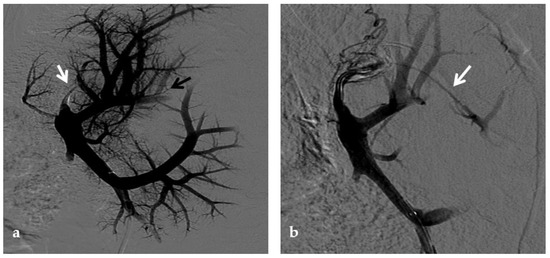

Figure 8.

Right oblique anterior (30° cranial) view of a transjugular retrograde portography performed in a 9-year-old female with extrahepatic portal vein cavernoma due to a neonatal umbilical vein catheterization and portal vein thrombosis, who complained of symptoms of portal hypertension. She was a candidate for Meso-Rex bypass surgery. The image shows retrograde filling of the intrahepatic portal vessels with the complete visualization of the Rex segment (arrow) after wedged left hepatic venography. Meso-Rex bypass was then surgically performed.

Conventional non-invasive imaging (CDUS, CT, MR) is not always reliable in assessing the patency of the native intrahepatic portal venous system and/or the Rex segment of the left portal vein in patients with cavernoma. At CDUS examination differentiating intrahepatic portal venous branches from venous collaterals in patients with the impaired portal venous flow can be challenging. Similar problems are faced by MR. One study compared MR and retrograde portography for the assessment of the Rex recess in children with extrahepatic PVT before Meso-Rex shunt surgery, demonstrating that only retrograde portography was reliable [63] (Figure 8).

Retrograde portography is the gold standard imaging method to assess the intrahepatic portal venous system with high resolution: if patency of the native intrahepatic portal system is demonstrated, the surgical Meso-Rex bypass can be performed; vice versa, unnecessary operative explorations are avoided. A surgical spleno-renal (Warren) portosystemic shunt or a radiological transjugular intrahepatic portosystemic shunt (TIPS) can be proposed whenever intrahepatic vascular anatomy is compromised [66]. The choice between the two different approaches is based on other findings such as the presence of a prevalent cavernous vessel to land with the TIPS, the distance between the splenic and the left renal vein to make a surgical shunt, and local expertise/resource availability.